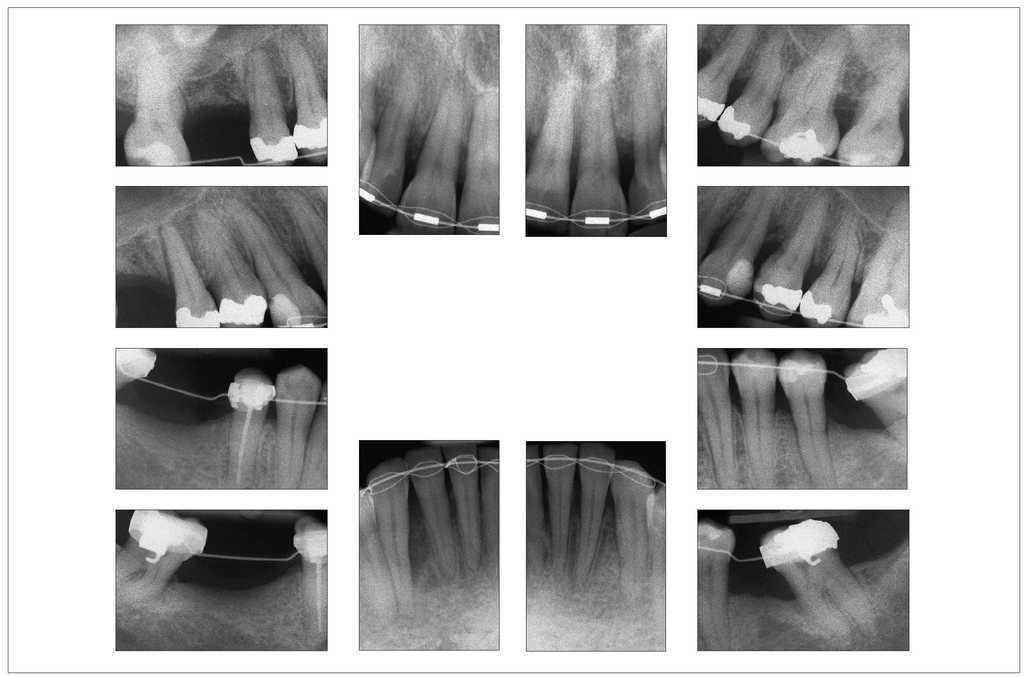

Uno o dos años después de iniciar el tratamiento, el cuadro es clínicamente y radiológicamente estable con una ganancia de inserción clara y profundidades de sondaje fisiológicas incluso en los dientes 31 y 21, cuyo pronóstico inicial era desfavorable (figs. 7 y 8a a 8c). El odontólogo que derivó al paciente puede asumir a partir de este momento el tratamiento restaurador posterior.

Figura 7. Imágenes radiográficas del 13/3/2008, 1 año después de la intervención: se aprecia una ganancia de inserción clara al cabo de sólo 9 meses del tratamiento ortodóncico «activo».

Figura 8. Situación clínica dos años después del inicio del tratamiento: se aprecia un periodonto estable sin alteraciones.